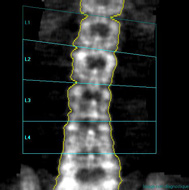

Deux sites sont analysés, le rachis

lombaire et le col fémoral Un système informatique analyse l’absorption

des Rayons X par le squelette et en déduit la densité minérale osseuse

(DMO). Celle-ci est comparée à celle de femmes du même âge (Z score)

et de trente ans (T score). C’est la diminution sensible du T score qui

permettra d’affirmer l’installation de l’ostéoporose. |